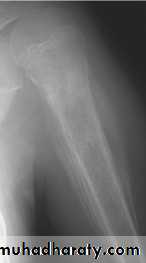

The sign & findingsWide zone of transition is being

Benign or malignant ????Codman's triangle

Elevation of the periosteum at the side of the tumor marginlytic, expansile lesion, Sub articular in location give the soap bubble appearance

Giant cell tumoronion peal periosteal reaction

Codman's triangle is a type of periosteal reaction seen with aggressive bone lesions could be singlelayer and mulitlayered periosteal reaction), only the edge of the raised periosteum will ossify.